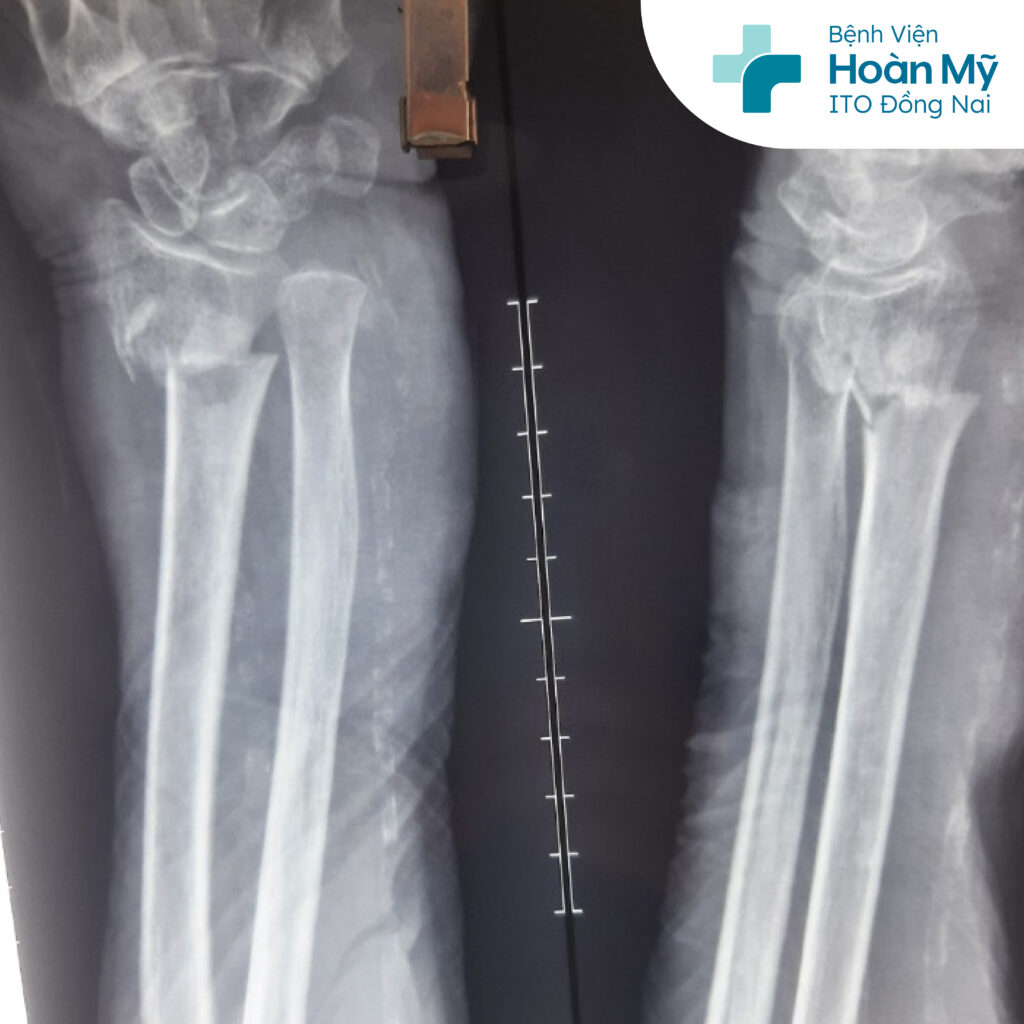

Hình ảnh X-Quang gãy đầu dưới xương quay

Nhận định đây là bệnh nhân tuổi cao hiếm gặp, nguy cơ xảy ra rủi ro trong và sau phẫu thuật cao, nên các bác sĩ đã hội chẩn giữa nhiều chuyên khoa để tầm soát bệnh lý đi kèm và tiên lượng trước nguy cơ để có phương án phẫu thuật đảm bảo an toàn nhất cho người bệnh. Bệnh nhân được Bs CKI Hoàng Đức Mạnh - Khoa Chấn thương chỉnh hình và ekip tiến hành phẫu thuật kết hợp xương bằng đinh kirschner.

Ca mổ diễn ra trong khoảng 30 phút, nhờ thực hiện phẫu thuật nhanh và sự phối hợp ăn ý giữa bác sĩ phẫu thuật và gây mê hồi sức, kết thúc ca phẫu thuật an toàn, bệnh nhân về khoa tỉnh táo. Sau 1 ngày phẫu thuật, bệnh nhân ổn định, ăn ngủ tốt, đỡ đau tại chỗ, vết mổ khô không sưng.